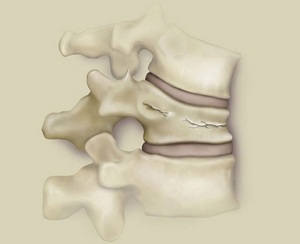

Компресійний перелом хребта являє собою травму хребців, яка виникає при одночасному згинанні і стисненні. В результаті цього хребець стискається і тріскається. Форма хребця при цьому стає клиноподібної, якщо сплющивание пройшло по передній частині. Якщо ж перелом хребця значний, то це загрожує здавленням або пошкодженням спинного мозку через те, що задня частина деформованого хребця впивається в спинномозковий канал.

Залежно від розміру деформаціїхребців виділяють 3 ступеня переломів. Для першого ступеня характерно зниження висоти хребця на менше, ніж 1/3. Така форма є стабільною. При 2-го ступеня зниження хребця відбувається на половину його висоти. При третього ступеня деформується більше половини тіла хребця. 2 і 3 ступеня є нестабільними і при них спостерігається патологічна рухливість хребців.